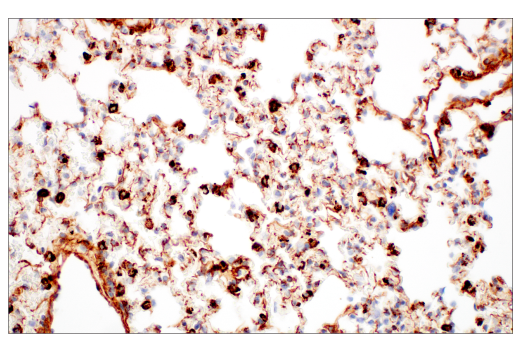

Immunohistochemical analysis of paraffin-embedded mouse lung using EphA2 (D4A2) XP® Rabbit mAb.

Immunohistochemistry Image 6: EphA2 (D4A2) Rabbit Monoclonal Antibody